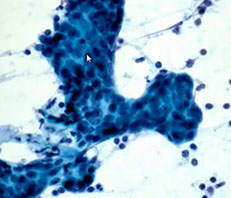

Acinic cell carcinoma

2nd MCC salivary gland malignancy in minor salivary glands in adults (up to 6% of all neoplasms and 1/5 malignancies); usually in the parotid gland of women in the 5th-6th decade

- well-circumscribed, slowly growing mass that is occasionally painful

Cellular smears c loosely cohesive polygonal bland serous acinar cells c eccentric nuclei in background of naked nuclei and lymphs

- abundant granular / vacuolated cytoplasm c indistinct cell borders, round uniform nuclei and small nucleoli c cytoplasm that is foamy to coarsely granular +/- psammoma bodies

- BVs can be seen in some clusters (perivascular tumor growth)

- may have intranuclear pseudoinclusions

- mits are infrequent

IHC: cells have PAS-(+) diastase-resistant zymogen granules in cytoplasm, keratin, alpha-1-antichymotrypsin, alpha amylosa, VIP, myoep markers, can have focal NE staining

DDx: normal parotid gland (tumors lack striated and interlovular ducts, lack lobular architecture)